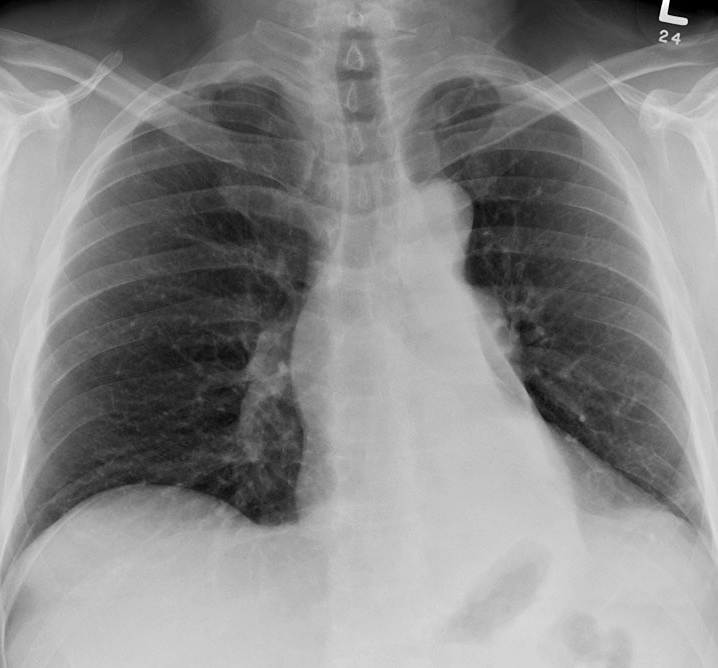

LLL Collapse Case 9